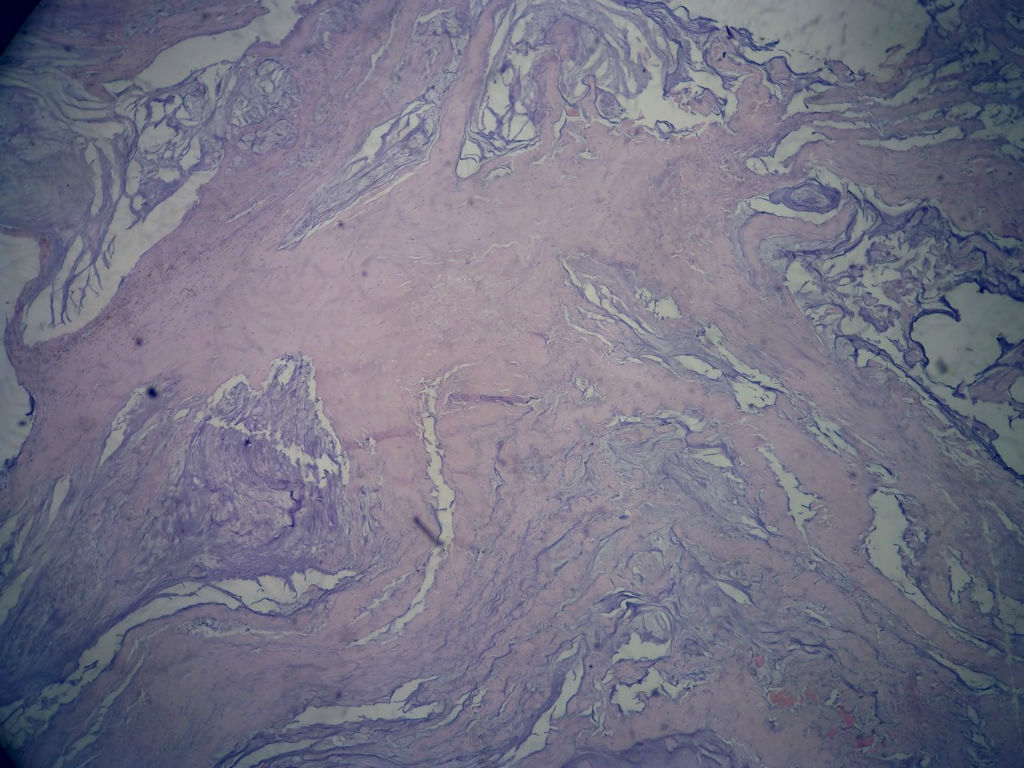

女,80岁,阑尾区肿块。

送检为不规则组织多块,粘滑,解剖结构辨认不清。术中探查双侧卵巢无异常。

阑尾粘液性肿瘤,癌的可能性大

粘液长在肌层,而且漂浮着可疑上皮细胞,最大可能粘液腺癌。